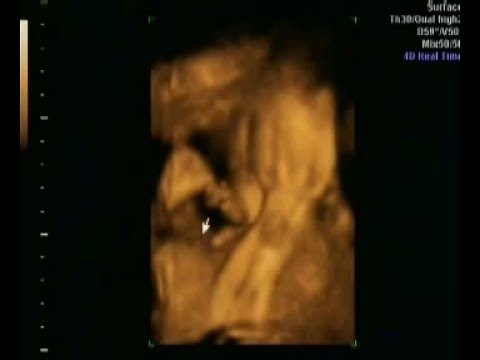

Artikler om graviditet

Mad og Graviditet – Hvilken kost bør du spise når du...

Spørgsmål om graviditet

Spørgsmål om fødsel

Graviditetsberetning

Fødselsberetning